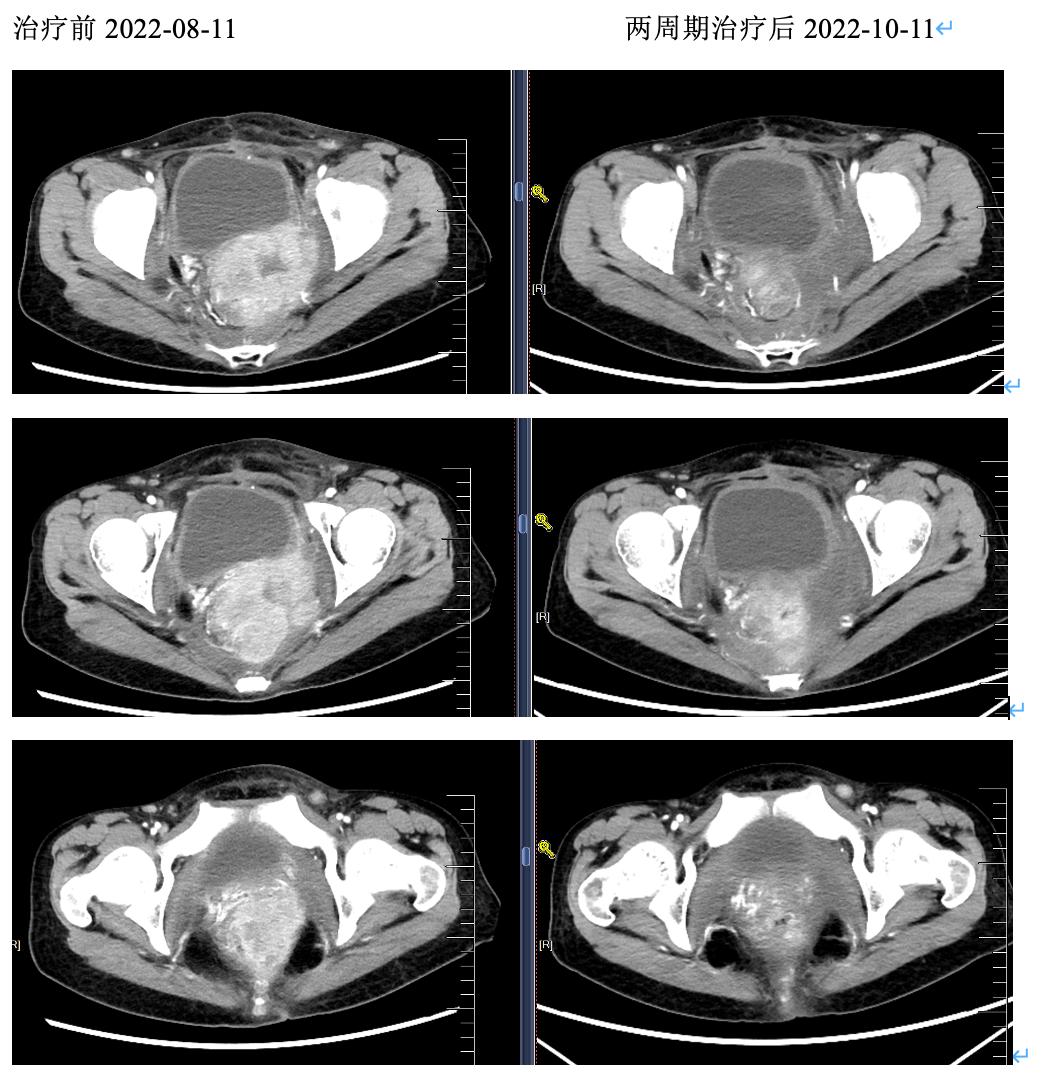

疗效评价:治疗后患者直肠出血明显减少,肛门坠胀痛明显减轻,贫血改善无需再输血。影像学提示盆腔病灶明显缩小达PR;瘤内注射区域液化坏死,肿瘤缩小较非瘤内注射区域更显著。血肿瘤指标SCC由治疗前的1410ng/ml降至55ng/ml。

第一周期瘤内注射前肿瘤穿刺活检病理提示为转移性鳞癌;第二周期瘤内注射同一部位穿刺活检病理提示:慢性炎性细胞浸润,未见癌细胞 。

图4. 治疗前后CT:盆腔病灶明显缩小,瘤内注射区域肿瘤缩小较非瘤内注射区域更显著。